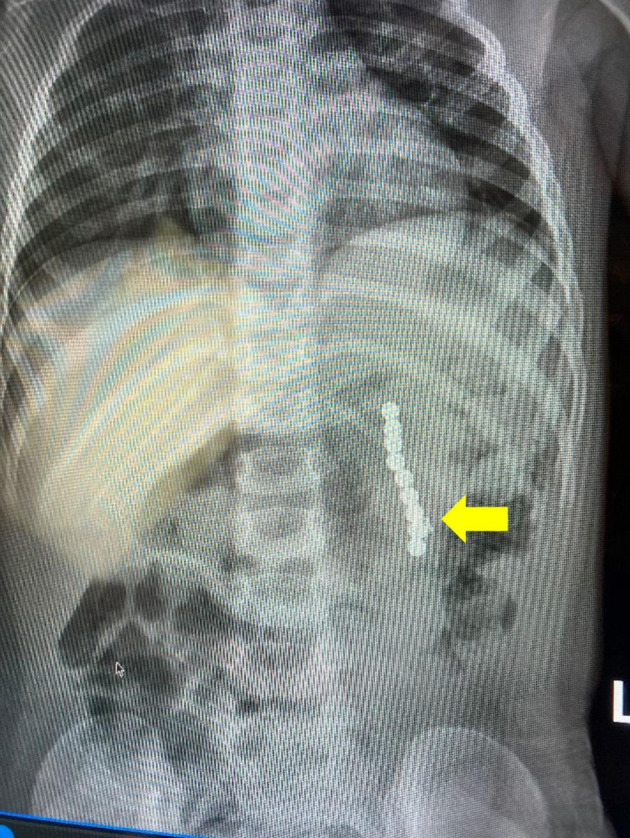

在磁共振成像(MRI)等强磁场存在的情况下,铁磁性物体可能成为病人或医护人员受伤的源头。为防止此类问题的发生,在进行核磁共振成像之前必须对患者和医护人员进行仔细筛查,以确定核磁共振成像的禁忌症,包括外部或内部铁磁性产品的存在。我们为您介绍一名 2 岁 11 个月大的患儿,他前来进行核磁共振成像检查,以评估潜在的脊椎异常。在最初的扫描和图像采集过程中,发现图像失真,随后确定是摄入的磁性物体造成的。本文讨论了核磁共振成像的基本原理,介绍了防止患者和从业人员因铁磁性物体而遭受风险的安全途径,并回顾了之前有关内部铁磁性装置对患者造成不良影响的报道。

In the presence of a strong magnetic field such as for magnetic resonance imaging (MRI), ferromagnetic objects may become a source of patient or healthcare provider injury. To prevent such problems, careful screening of patients and healthcare workers is mandatory prior to MRI to identify contraindications to MRI including the presence of external or internal ferromagnetic products. We present a 2-year, 11-month-old child who presented for MRI to evaluate a potential vertebral anomaly. During initial scanning and image acquisition, image distortion was noted which was subsequently determined to be the result of ingested magnetic objects. The basic principles of MRI are discussed, safety pathways to prevent patient and practitioner risk related to ferromagnetic objects presented, and previous reports of patient-related adverse effects from internal ferromagnetic devices reviewed.